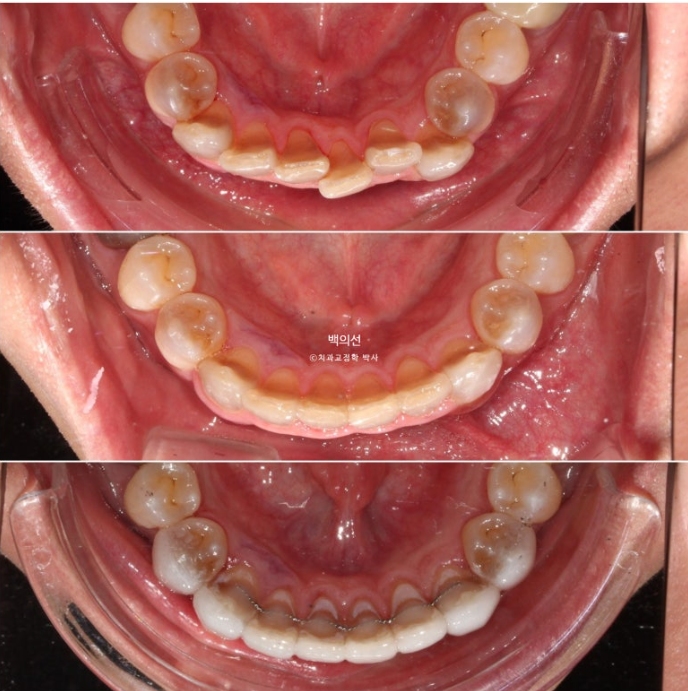

In the lower front teeth, there are varying heights in addition to the canine crowding.

The lower front teeth have stricter conditions for no-prep laminate than the upper front teeth.

Because the laminate has to wrap around the incisal edge of the lower front teeth, there needs to be some distance between the upper front teeth and the lower front teeth.

This is what the Gelami looks like on the 8 lower front teeth.

Now let’s compare the initial visit, after orthodontic treatment, and after Gelami in sequence.

This is an occlusal surface photo that gives an idea of the thickness of Gelami.

23.12~25.06